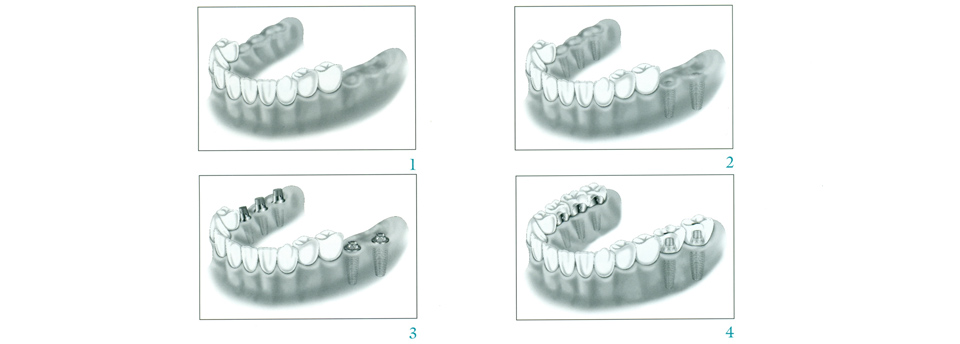

Missing teeth can be a nuisance, both cosmetically and functionally; you may feel self-conscious about a gap in your smile, and that gap will almost certainly cause problems with biting and chewing. While there are several procedures dentists use to fill in gaps left by missing teeth, dental implants are by far the most natural-seeming in form and function. A dental implant is nearly indistinguishable from a natural tooth and can last a lifetime with proper maintenance. Click here to find out more.